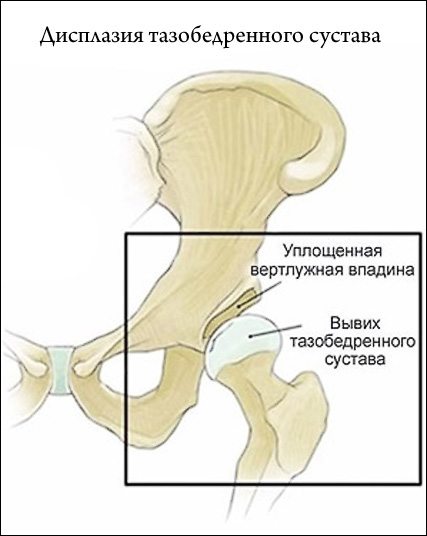

Огляд дисплазії тазостегнових суглобів у новонароджених: причини, діагностика, лікування